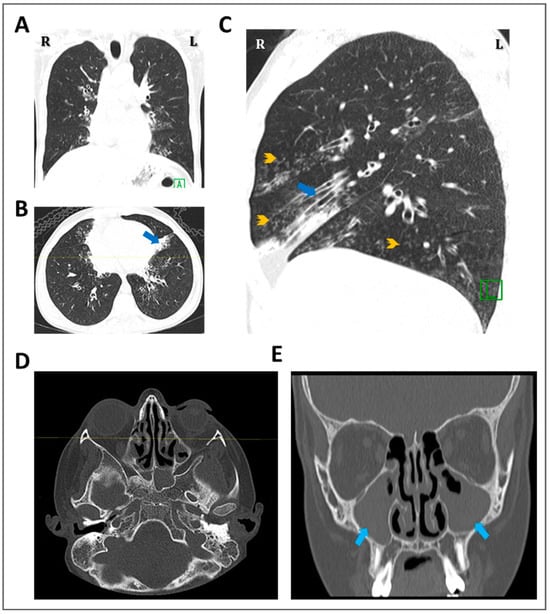

3.3. Detection of Ultrastructural Defects of the Cilia